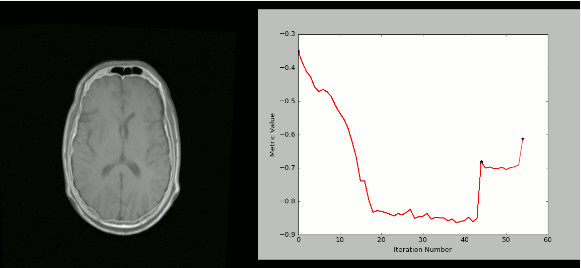

使用SimpleITK和Python创建可视化的严格CT / MR配准过程: